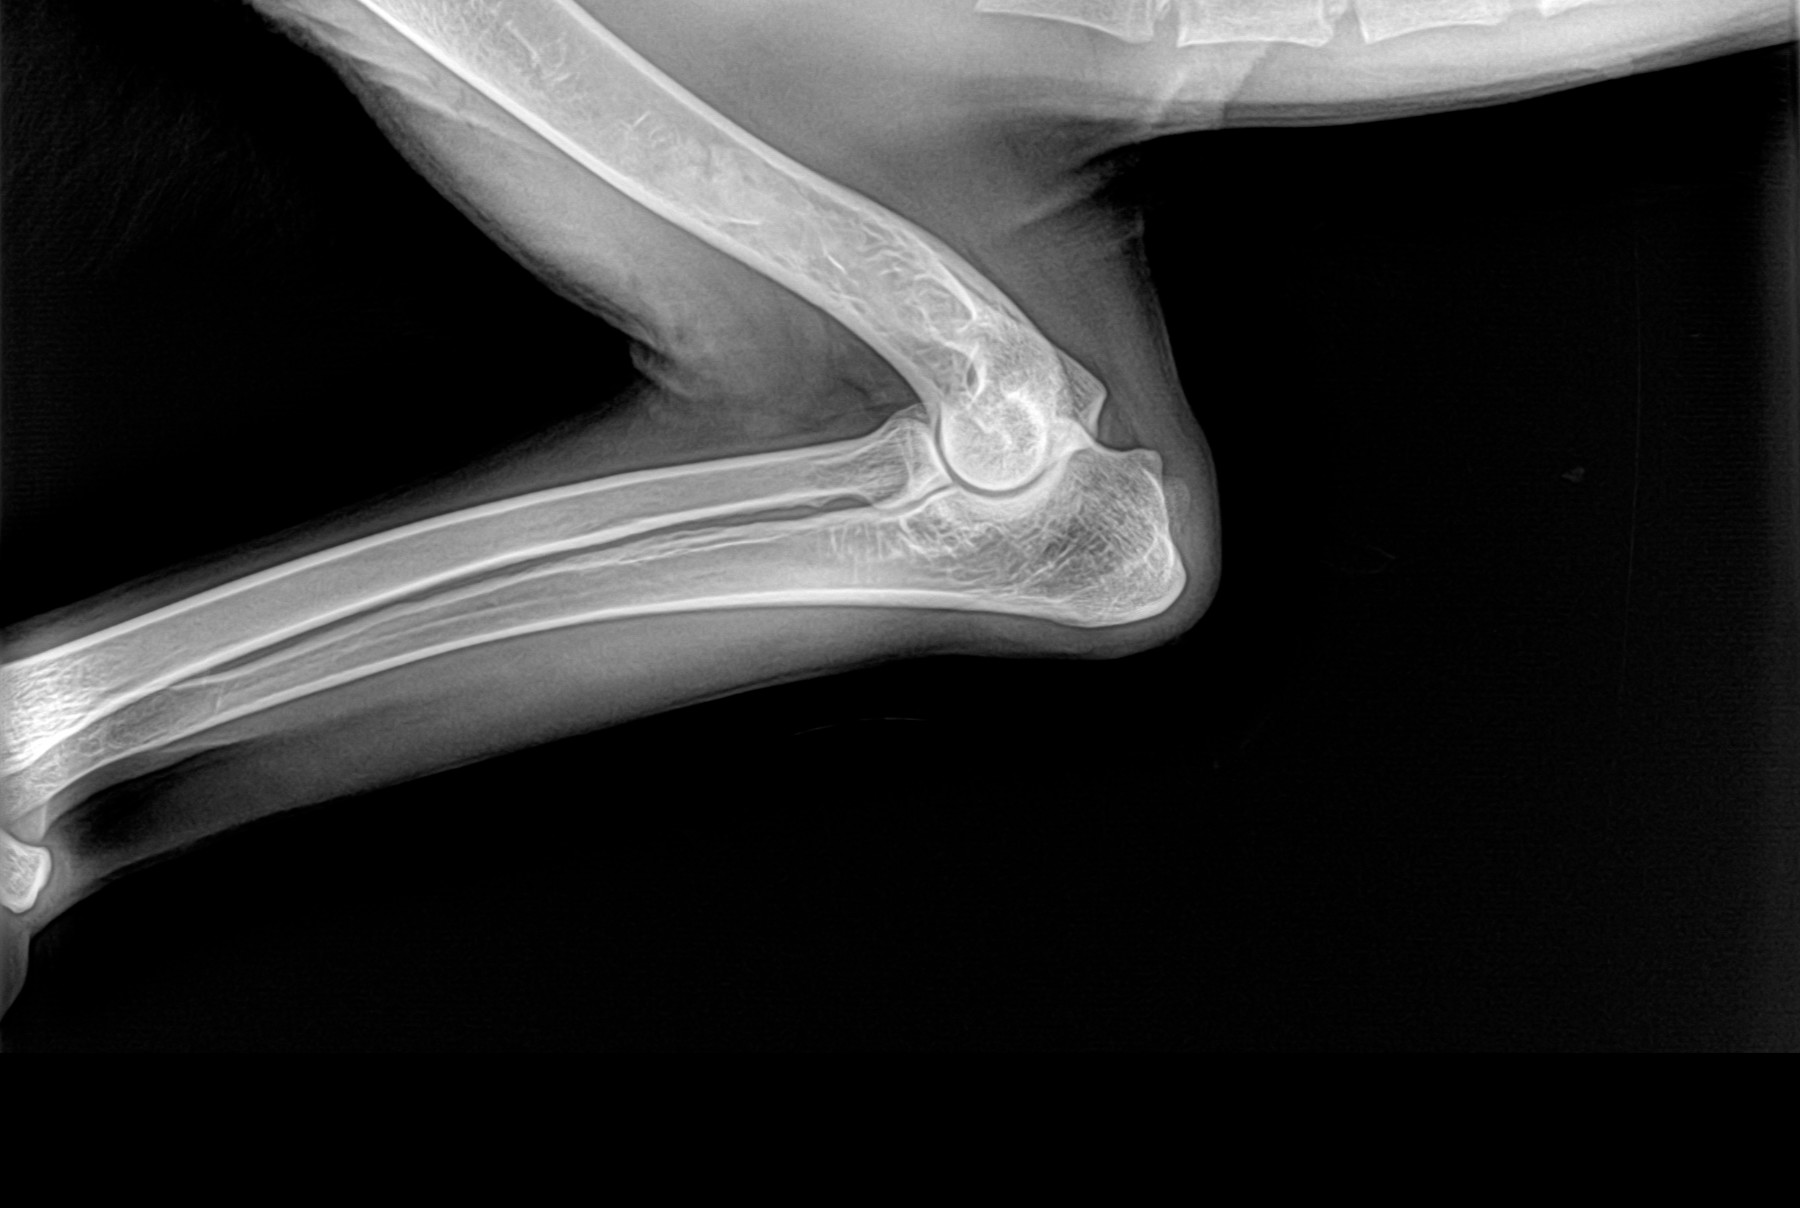

Radiología Digital como Herramienta Complementaria en el Dictamen de Bienes Muebles